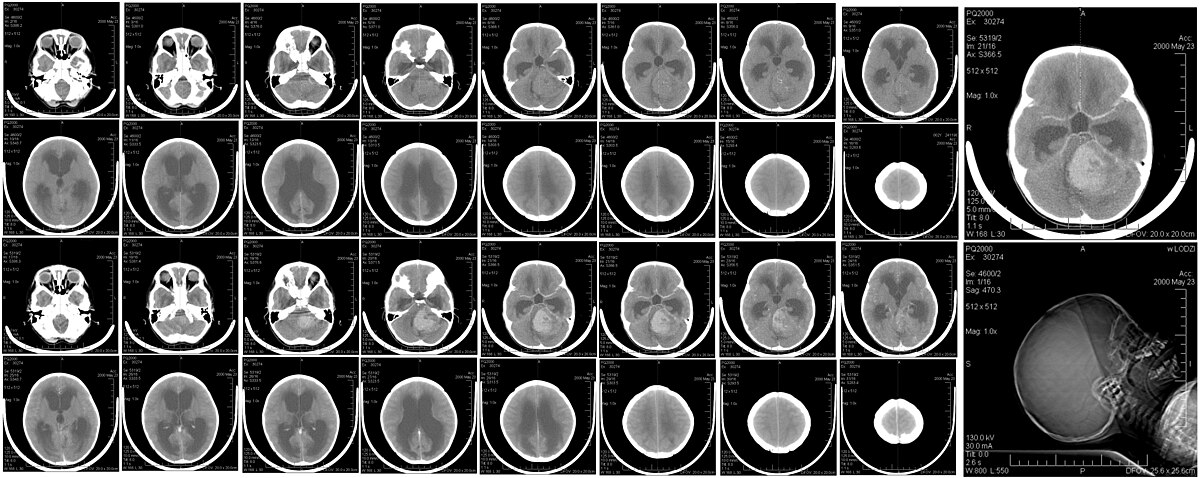

CT Brain Scan

Imagem de TC do cérebro, usada em neurologia. Fonte: Wikimedia Commons

A TC é utilizada em diversas áreas, incluindo:

• Neurologia: Detecção de AVC, tumores e hemorragias.